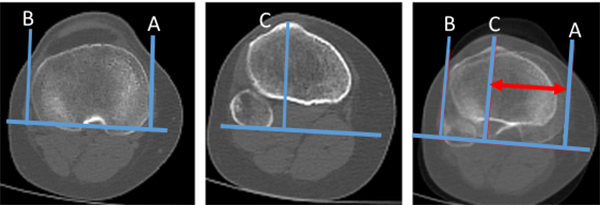

Lateralización del TAT

Esta medición se realiza en extensión completa de rodillas. Es una proporción determinada a partir de dos imágenes de la epífisis proximal de la tibia.

Una de ellas es donde se visualiza el platillo tibial en su mayor diámetro transversal con otra imagen donde se visualiza la inserción del tendón rotuliano en el tubérculo tibial anterior. Ya superpuestas estas imágenes, trazaremos una línea basal que pasará por el borde posterior de la meseta tibial. A partir de ahí, mediante líneas perpendiculares, determinaremos dos distancias que representarán el diámetro transversal mayor de la epífisis proximal de la tibia entre los bordes medial (punto A) y lateral (punto B): distancia A-B.

La otra distancia será la comprendida entre el centro de inserción el tendón rotuliano en el tubérculo tibial anterior (punto C) y el borde medial del platillo tibial (punto A): distancia A-C. La lateralización del TAT se calcula como un porcentaje del ancho de la tibia: A-C / A-B x 100. Ando encontró 64% ± 6% en grupo control y 79% ± 9% en grupo con inestabilidad.13 Prakash encontró 60.7% ± 3.1 en grupo control versus 64.1% ± 2.8 en grupo con inestabilidad14 (fig. 10).

Figura 10: Lateralización de tuberosidad tibial. Se calcula mediante la superposición de dos cortes, uno donde se visualiza la parte más ancha de tibia proximal, y otro corte donde se visualiza la inserción del tendón patelar en TAT. Se marcan tres líneas perpendiculares a la cortical posterior de tibia superior. A) Pasa por cortical medial. B) Pasa por cortical lateral de tibia. C) Pasa por el centro de inserción del tendón patelar. La lateralización se calcula: A-C/A-BX x 100. Se estima el porcentaje de la lateralización.